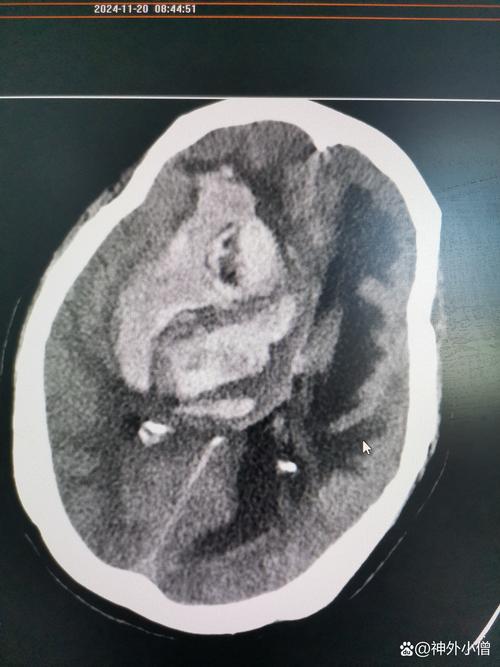

- 快速诊断: 立即进行头部CT扫描,这是诊断脑梗和排除脑出血最快速、最有效的方法,同时评估是否有脑疝形成。